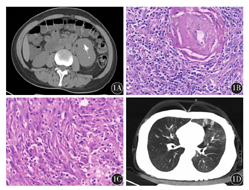

患者,女性,45岁,因全身皮疹、口腔溃疡2周入院,主要表现为全身多处皮肤暗红色斑丘疹、瘙痒,口腔多发溃疡,伴乏力,无发热、盗汗及消瘦。查体:口唇黏膜溃疡,其上见血痂覆盖,扁桃体不大,肝肋缘下2 cm,脾肋缘下1 cm。血常规示:白细胞计数(WBC)8.68×109/L,血红蛋白(Hb)144 g/L,血小板计数(Plt)312×109/L。血生化示:白蛋白25.7 g/L,乳酸脱氢酶254 U/L,β2微球蛋白、球蛋白、肝肾功能及电解质等正常;红细胞沉降率27 mm/1 h;血清蛋白电泳及免疫固定电泳未发现异常条带。术前传染病筛查和EB病毒DNA均阴性。左前臂病变皮肤活组织检查:表皮基底细胞广泛液化变性,真皮乳头组织疏松,密集淋巴细胞、组织细胞浸润,提示PNP。全腹CT示:左侧腹膜后包块,双侧腋窝及腹膜后淋巴结肿大(图1A)。腹部B型超声示:左中下腹探及低回声团块,考虑肿物为肾上腺来源。收入泌尿外科行腹部包块切除术,肉眼观察肿物呈结节状,大小7.8 cm×5.5 cm×9.2 cm,薄膜完整,切面灰白色,质地中等;显微镜下可见淋巴组织增生,淋巴滤泡形成,其中小血管增生,血管壁增厚伴透明变性(图1B)。滤泡间见大量梭形细胞,呈束状、席纹状排列;细胞边界不清,呈合体状;胞质较丰富,呈嗜酸性;核呈卵圆形或圆形;核质呈颗粒状,嗜碱性(图1C)。免疫组织化学示:淋巴细胞CD3+、梭形细胞CD21+、CD23+、vimentin+、CD68+、SAM+、S-100+、bcl-2+、CK-、CD117-、desmin-,Ki-67阳性率10%~15%。符合CD合并FDCS。遂转入血液科,采用CHOP方案化疗,皮疹消退,口腔黏膜溃疡愈合。第4个周期化疗结束后,患者突发憋闷、气促,伴发热,无咳嗽、咳痰。查体:体温波动于37.8~38.9 ℃,左肺呼吸音降低,偶可闻及少许哮鸣音。血气分析:pH值7.41,PO2 68 mmHg(1 mmHg=0.133 kPa),PCO2 33 mmHg(吸氧4 L/min时),提示低氧血症,降钙素原及C反应蛋白正常,多次G试验及血培养阴性。肺功能检测示:重度阻塞性通气障碍(FEV1% pre:45%,FEV1/FVC:38%),弥散功能正常,支气管扩张试验阴性。胸部CT示:左肺密度不均匀,呈马赛克样分布,肺中叶支气管扩张(图1D)。经呼吸科及重症监护室(ICU)会诊后诊断为OB,予以大剂量糖皮质激素、吸入激素、扩张支气管等治疗后,呼吸困难进行性加重,治疗46 d后因呼吸衰竭死亡。

1A:腹部CT示腹膜后见低密度包块,边界清楚,其中见辐射状钙化影;1B:腹膜后肿物淋巴组织增生,其中见透明样变小血管 HE ×200;1C:腹膜后肿物滤泡间呈束状或席纹状分布的梭形细胞 HE ×200;1D:胸部CT示左肺见不均匀斑片状低密度影,呈马赛克样分布,并见支气管扩张